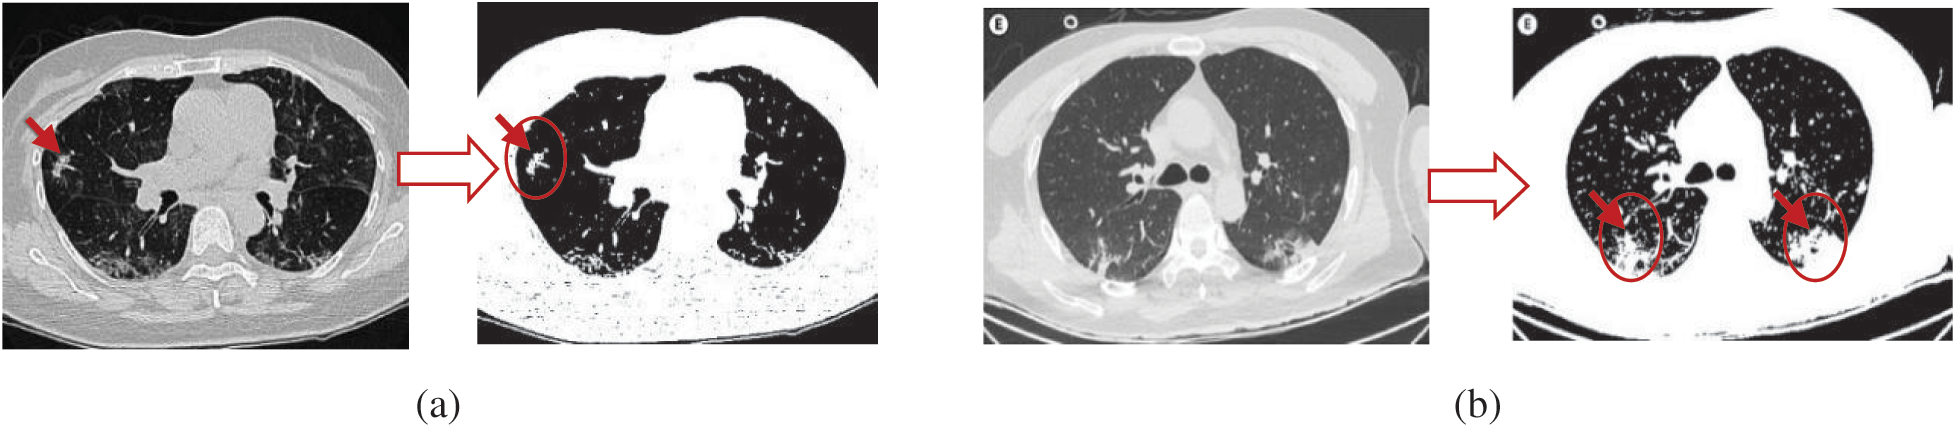

A detailed overview of the proposed AIMDP model is shown in Fig. 3. The model starts with patient information input; this information contains the raw CT image data of suspected patients. The pre-processing phase handles any noise or missing data in the original dataset. Missing data are replaced statically with substituted values. A Gaussian function is used to reduce the noise by blurring the image. The CT images are then sorted into classes based on their features and attributes to extract the significant pulmonary region. A deep learning technology based on CNNs is used in the segmentation phase. CNN’s were initially proposed for image segmentation by Badrinarayanan et al. [23]. Different filters are applied in CNNs to capture the relevant features from an image using predefined parameters and learned weights at every level. In this phase, the following sequences of layers are presented: (1) The maximum pooling (Max Pool) layer is used to reduce the CT image features by summarizing the most stimulated occurrences of a part. (2) The convolution layer is used to convolve a kernel (filter) of weights to extract the features. (3) The pooling layer uses statistical data about the surrounding features to reduce the resolution. In this layer, the maximum pooling method is used to downsample the input features by using filters to detect the maximum number of regions to be applied to feature maps. In other words, it calculates the maximum value for each patch in the feature map. (4) The dense layer searches for specific patterns in pixel values and groups features with the same patterns in specific classes. This means that a dense layer classifies one object into two classes by generating the output (None, 2). To do so, the loss function is selected based on the number of classification categories, which is 2, and then uses the binary cross-entropy loss function. That is used to run the model by calculating the loss and gradient for each pixel and then implementing the back-propagation process. The segmentation phase is used to process the loaded CT images in a limited time for the early diagnosis of COVID-19. A sample of the CT image output from the AIMDP model is shown in Fig. 4.

Figure 4: Examples of CT image output from the AIMDP model

The segmentation phase splits all CT images into patches, and then these patches are used as input to the trained CNN. Concurrently, a label is assigned to each patch to represent each feature detected, as shown in Algorithm 1. These labels are then collected to represent the CT key features found, e.g., GGO, SWC, CPP, pleural effusions, large lymph nodes, and lung cavities. The final results of the segmentation of the lung region are obtained by collecting these features. The augmentation is applied to the training data using Algorithm 1 (Fig. 5). The data are transformed into a NumPy array with size [X, Y, Z] for each segment.